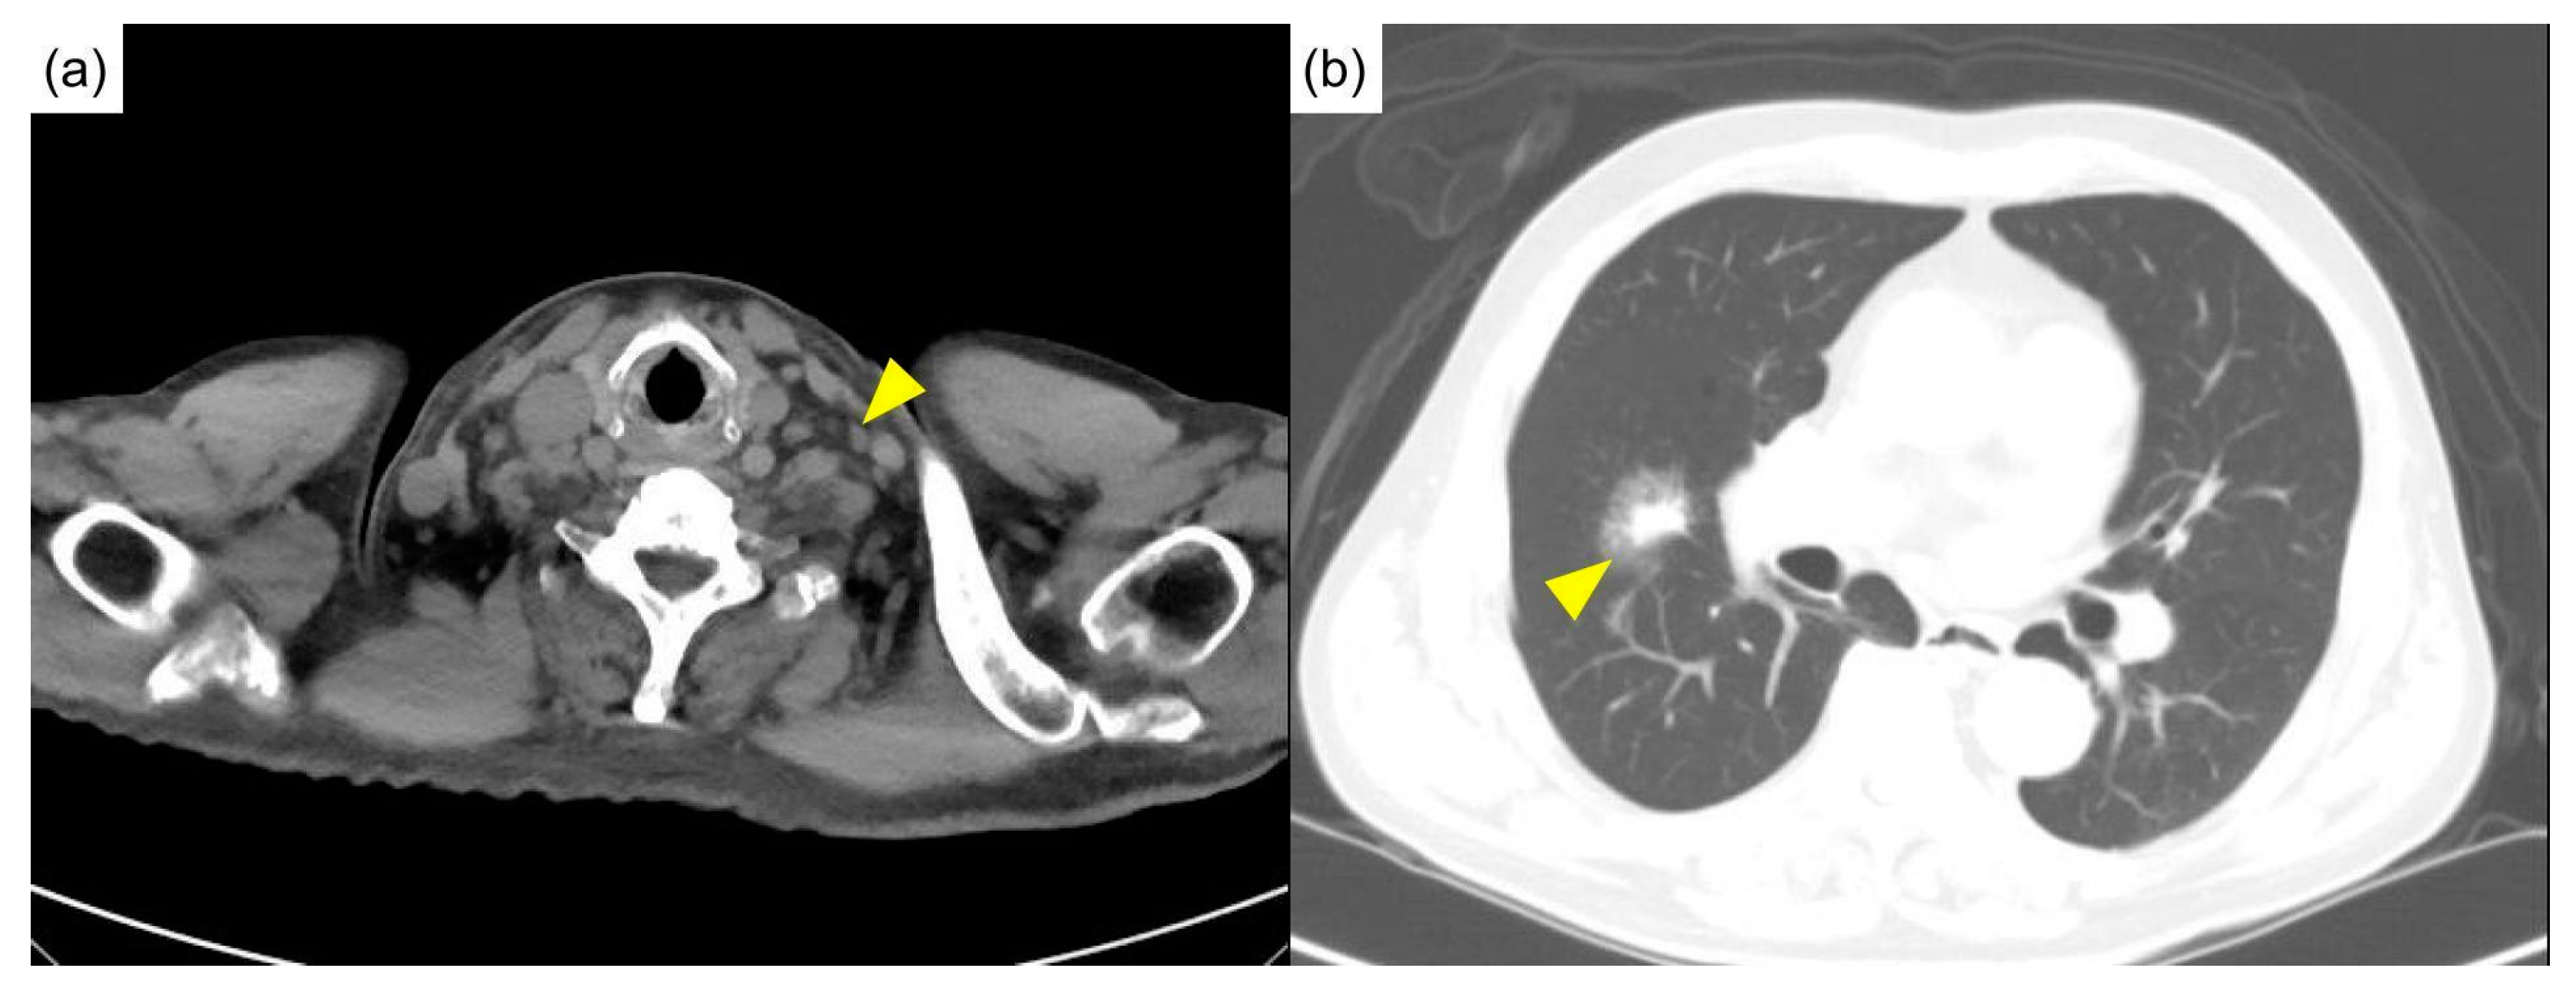

With anemia and pulmonary involvement, our patient fulfilled the criteria for severe iMCD [5]. He was treated fortnightly with tocilizumab, a humanized anti-IL-6 receptor monoclonal antibody, at 8 mg/kg intravenously. An initial high dose of glucocorticoids was prescribed and gradually tapered off in the subsequent 5 months. The patient has been regularly followed-up at our rheumatology clinic for 4 years with clinical improvements (hemoglobin, 12.7 g/dL; albumin, 4.1 g/dL; CRP, <0.1 mg/dL; and IgG4, 445 mg/dL) and shrinkage of lymph nodes (Figure 5a), where the size of lung mass modestly reduced from 3.11 cm to 1.69 cm (Figure 5b).

Figure 5.

The latest computed tomography after 4 years of treatment. (a) Shrinkage of lymph nodes (arrowhead) was noted. (b) The size of the lung mass modestly reduced from 3.11 cm to 1.69 cm (arrowhead).